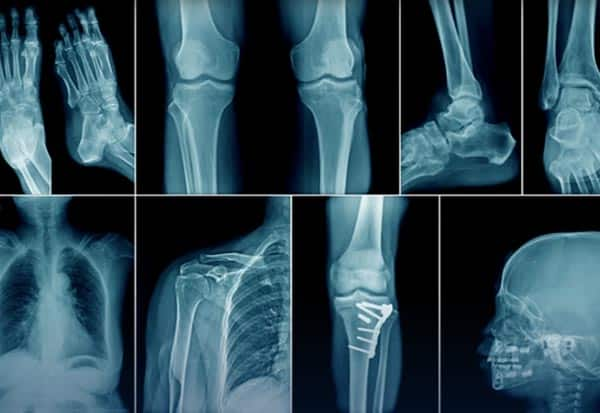

நவீன மருத்துவத் துறையில் கதிரியக்கவியல் (ரேடியாலஜி) நிபுணர்களின் பங்கு முக்கியமானது. ஜெர்மனி இயற்பியலாளர் ரான்ட்ஜென் 1895 நவ.8ல், 'எக்ஸ்-ரே' கருவியை கண்டுபிடித்தார். இவரது சாதனையை அங்கீகரிக்கும் விதமாக நவ. 8 உலக கதிரியக்கவியல் தினம் கடைபிடிக்கப்படுகிறது. எலும்பு முறிவு, காயங்களின் தன்மை உட்பட உடலுக்குள் ஊடுருவி சென்று படம் பிடித்து காண்பிக்கும் 'எக்ஸ் -ரே' பல வழிகளிலும் பயன்படுகிறது. ரான்ட்ஜெனின் கண்டுபிடிப்புக்கு 1901ல் இயற்பியலுக்கான நோபல் பரிசு வழங்கப்பட்டது.